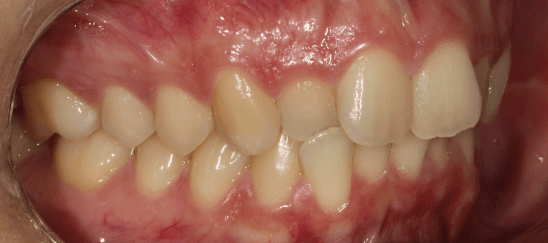

Križni griz

Ko ugriznete, vaši zgornji zobje padejo v spodnje zobe, kar je nasprotno, kot bi moralo biti. To se lahko zgodi z enim zobom ali s skupino zob in se lahko pojavi kjerkoli v ustih.

Zakaj ga popraviti?

Križni griz samo prosi za težave. Običajno se pri križnem ugrizu žvečilni robovi vaših zob ne ujemajo tako, kot bi morali, zato se vsa vaša žvečilna in grizna sila prenese na napačne površine pod napačnimi koti. Lahko bi začeli opažati recesijo dlesni, zlomljene zobe, obrabljene lise na zobeh in drugo.

Ali lahko nevidni aparati pomagajo?

Prej / Potem *